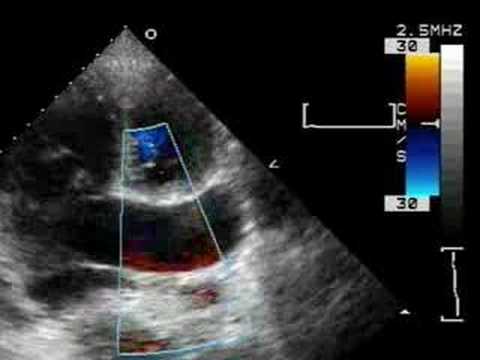

Transthoracic echocardiography of a congenital left ...

Transthoracic echocardiography of a congenital left ... from heart.bmj.com